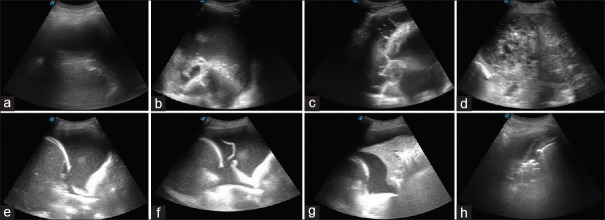

Methods: The files of patients who underwent thoracic USI and thoracentesis due to PF accumulation were retrospectively examined. PF sonographic patterns and pleural thicknesses were retrieved from the USI records. Based on the Light's criteria, PFs were classified into transudative PF (TPF) and exudative PF (EPF). A scoring system was established based on the sonographic patterns and pleural thickness. Sonographic scores and other clinical, radiological, and demographic characteristics of the two groups were comparatively analyzed.

Results: Among the 64 cases analyzed, 32 (50%) were categorized as TPF. The average pleural thickness in the TPF group was 1.4 mm. The hypoechoic sonographic pattern rate in the TPF group (75%) was significantly different from that in the EPF group (p < 0.001). A hypoechoic sonographic pattern (p = 0.002) and pleural thickness >1.5 mm (p = 0.031) were independent predictors of EPF. The scoring system demonstrated a sensitivity of 84.38% and a specificity of 75.00% for predicting EPF when the sonographic score was ≥3.

Conclusion: Thoracic USI can serve as a noninvasive method to predict the nature of PFs by combining sonographic patterns and pleural thickness.